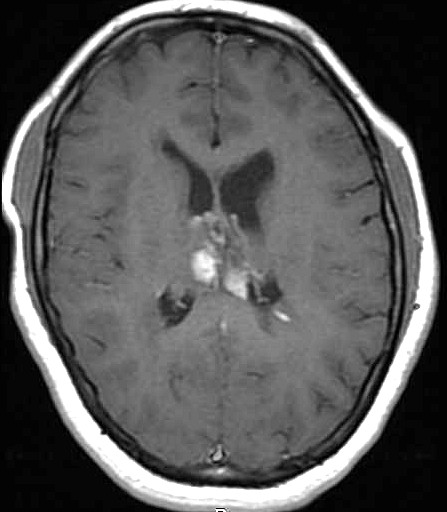

| Fem. 17a. |

| Nódulo sólido homogêneo preenchendo o III ventrículo, com limites precisos, com hipossinal em T1 e hipersinal em T2 e FLAIR, que se impregna por contraste paramagnético. Lesão menor implantada no assoalho do IV ventrículo provavelmente representa disseminação por via liquórica. |

| CORTES AXIAIS, T1 COM CONTRASTE | ||